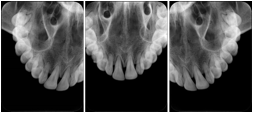

3. A dental provider wishes to capture a series of DICOM IO images for the patient’s dentition. The tooth morphology, teeth are divided into molars, premolars, canines and incisors, and a number of images for each jaw. The anatomic information was captured utilizing the triplet of schema. This standard code sequence is based on ISO 3950-2010, Dentistry - Designation system for teeth and areas of the oral cavity.

Every IO image should have anatomic information either through the primary or modifier sequence.

In most standard cases, images are oriented in structured layouts. These structured displays are useful to be shared between providers for reference purposes.

Table OO.1.1-1 shows structured display standard templates, where Viewset ID is based on the Japanese Society for Oral and Maxillofacial Radiology (JSOMR) classification provided by JIRA (Japan Medical Imaging and Radiological Systems Industries Association, www.jira-net.or.jp). Expected or typical teeth to be imaged location, region and designation codes are based on ISO 3950-2010, Dentistry - Designation system for teeth and areas of the oral cavity. For all the hanging protocols listed in OO.1.1-1, the value to use for Hanging Protocol Creator (0072,0008) is "JSOMR" and the value to use for Hanging Protocol Name (0072,0002) does not include "JSOMR" (e.g., "DL-S001A", not "JSOMR DL-S001A").